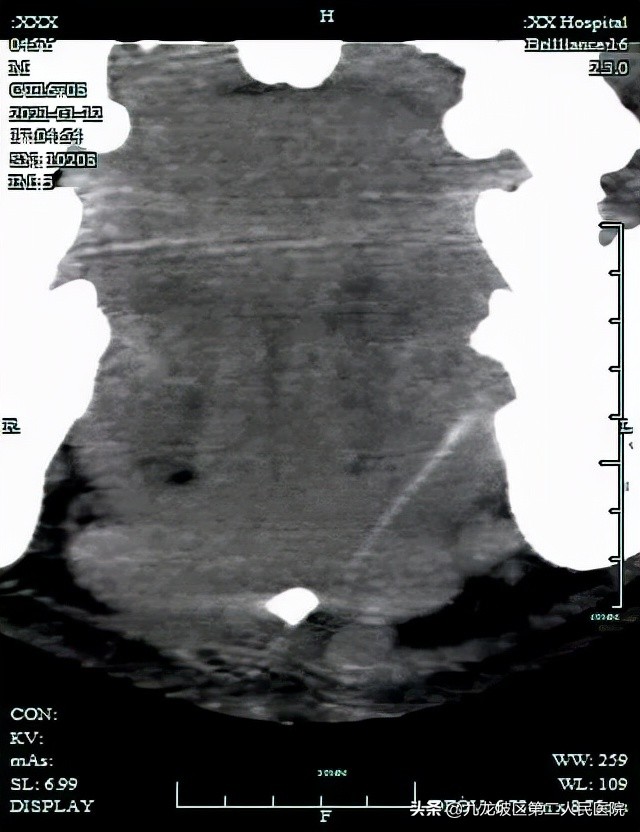

“CT扫描显示病灶位于舌骨上方,且与舌骨无明显关系,所以我们排除了甲状舌管瘘。”医生说,“在影像后处理工作站中行多种后处理,病灶全貌才得以显现。我们采用最大密度投影,最终发现颏下脓肿来自D7磨牙根尖脓肿,瘘管管径仅1mm。”